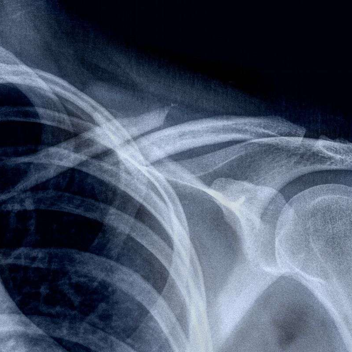

伴随损伤:相邻的胸锁关节和肩锁关节也必须进行临床检查。外周脉搏质量、皮肤颜色或血肿的检查可能提示动脉或静脉血管损伤。与锁骨相关的血管损伤少见,但具有潜在的致命性。预计 1–3% 的锁骨骨折患者伴有血胸或气胸。其他相关损伤涉及胸锁关节、肩锁关节和颈椎。罕见情况下,也会出现锁骨下动、静脉和臂丛神经损伤。在高速和极高速创伤中,伴随损伤可能性大,所有骨折都必须进行伴随损伤检查。多项研究表明,外侧三分之一骨折可导致肩袖损伤,尤其部分撕裂(如下图)。此外,还可能发生肱二头肌长头腱损伤,例如滑车损伤或上盂唇从前到后损伤 。